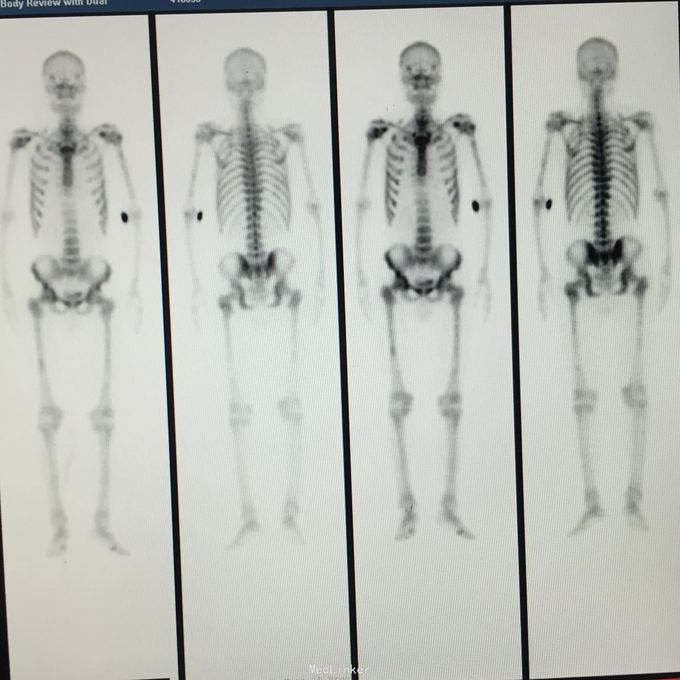

total PSA>100;前列腺磁共振平扫示:前列腺外周带左后方肿块,DWIBS信号明显增浓,考虑前列腺Ca。 行会阴前列腺穿刺活检术,病理示:前列腺腺癌。 全身骨扫描示:超级骨显像,符合前列腺Ca并多发骨转移。

前列腺癌并多发骨转移 处理:给予康士德,诺雷德,唑来磷酸等抗肿瘤治疗,提高免疫力等治疗,根据病情发展必要时给予放化疗及针对骨转移的锶89治疗